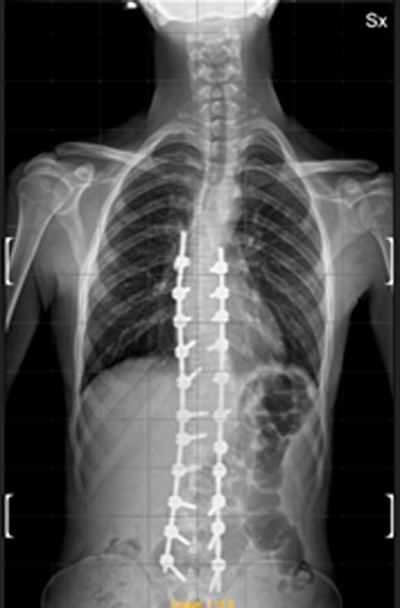

DIAGNOSI:

IPERCIFOSI DORSALE + SCOLIOSI DORSO LOMBARE

Radiografia della colonna in toto pre-operatoria

Intervento chirurgico eseguito:

STABILIZZAZIONE DORSO – LOMBARE CON OSTEOTOMIE CORRETTIVE

Radiografia della colonna in toto post-operatoria